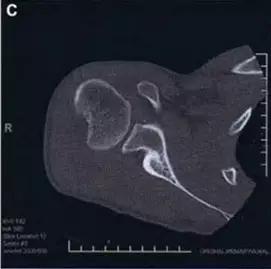

6. Jefferson 骨折

寰椎环的压缩性骨折,骨折是由枢椎压缩性外力引起,骨折多发生在寰椎前侧后侧以及侧方小关节。

第一颈椎双侧性前、后弓骨折,X 线片上很难发现骨折线,有时在正位片上看到 C1 关节突双侧性向外移位,侧位片上看到寰椎前后径增宽及椎前软组织肿胀阴影,CT 检查最为清楚,而 MRI 检查智能显示脊髓损伤情况。

A 图是稳定的 Jefferson 骨折(横韧带完整)轴位像。B 图是不稳定的 Jefferson 骨折(横韧带撕裂)轴位像